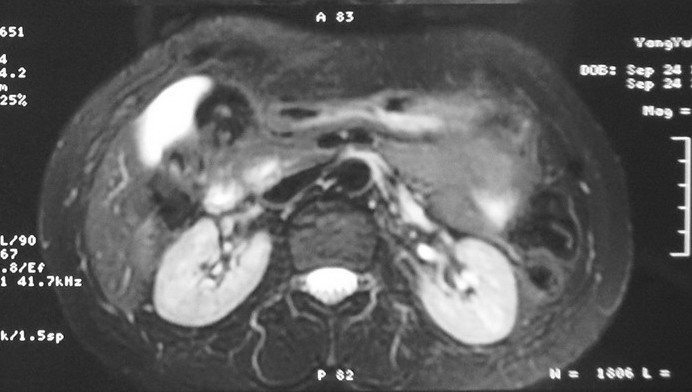

标题: MRI2066:腹膜后占位,请会诊,CT18531近期扫描图像

无明显不适,体检发现,

mri基本排除血管类肿瘤,明显强化说明极富血供,临床无症状,考虑胰岛细胞瘤可能大。

强化明显,并见有血管与之相连;考虑巨淋巴增生症.

极富血供的占位性病变,首先考虑良性,期待结果。